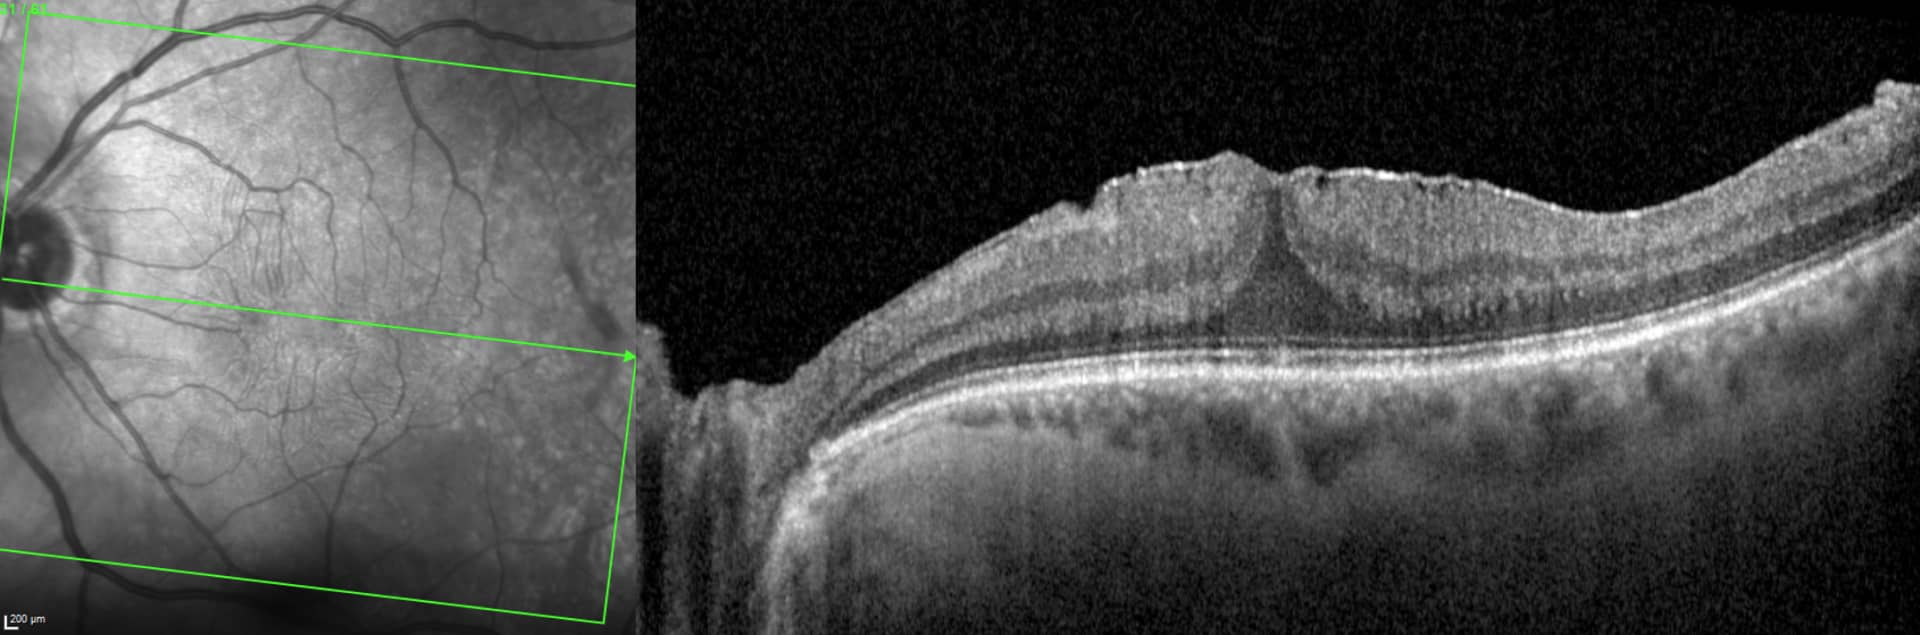

Les membranes épirétiniennes maculaires sont des proliférations gliales avasculaires à la surface de la rétine souvent limitées au pôle postérieur.

Il existe des membranes épirétiniennes idiopathiques, à la suite d’un DPV , ou secondaires (après rétinopathies vasculaires, inflammation intra-oculaire, hémorragie intravitréenne, déchirure rétinienne, chirurgie intra-oculaire…).

Les symptômes comprennent :

– Une baisse d’acuité visuelle

– Des métamorphopsies (lignes déformées)

– Micropsie/macropsie (anomalie de la taille des lettres)

– Diplopie monoculaire (vision double de l’œil atteint)

En cas de formes avancées symptomatiques, le traitement est principalement chirurgical en réalisant :

– Une vitrectomie centrale

– Un pelage de la membrane en question et de la membrane limitante interne .

concomitamment